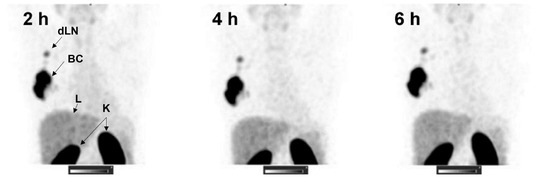

- Sandstrom, M.; Lindskog, K.; Velikyan, I.; Wennborg, A.; Feldwisch, J.; Sandberg, D.; Tolmachev, V.; Orlova, A.; Sorensen, J.; Carlsson, J.; et al. Biodistribution and Radiation Dosimetry of the Anti-HER2 Affibody Molecule 68Ga-ABY-025 in Breast Cancer Patients. J. Nucl. Med. 2016, 57, 867–871. [Google Scholar] [CrossRef] [PubMed]